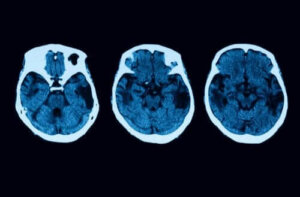

Diagnostiske tester slutter imidlertid ikke der. For å fjerne tvil, vil man også utføre andre nevrologiske tester som MR og tomografier. Hvis alt tyder på at du kan ha posterior kortikal atrofi, finnes det forskjellige behandlinger du kan velge mellom.